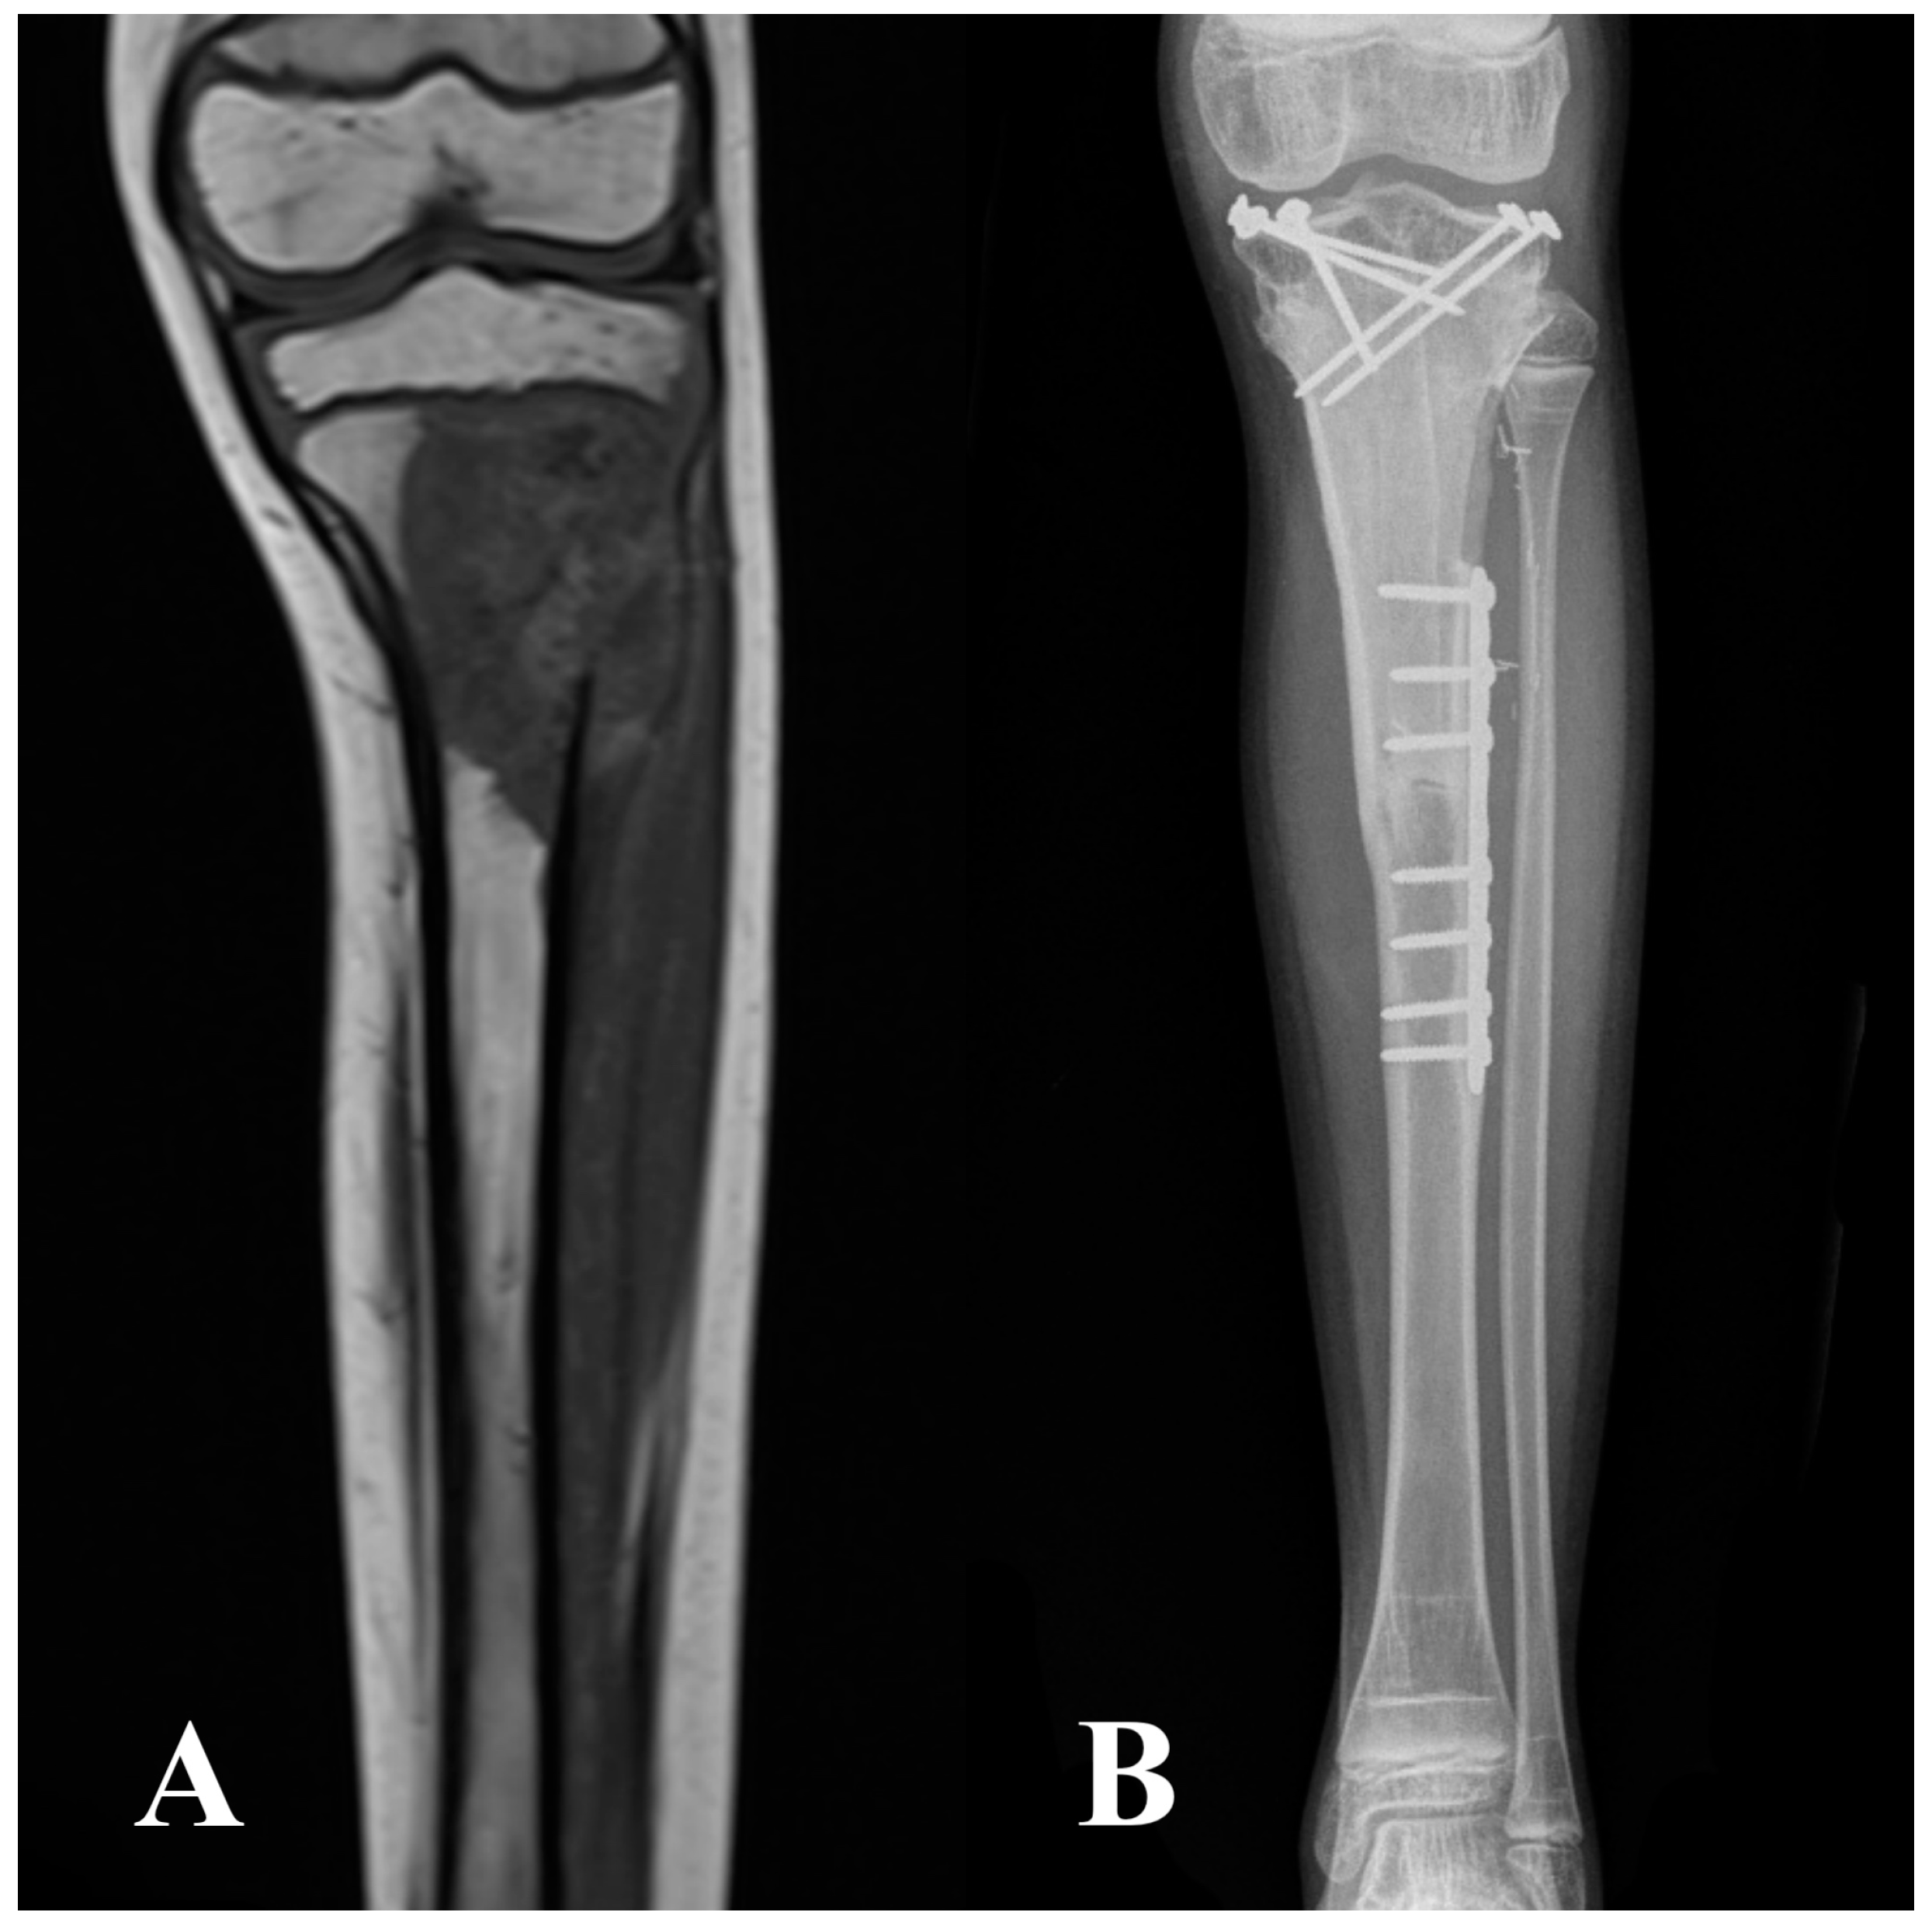

2.2. Surgical Technique, Aftercare, and Cancer Treatment

| Intercalary | 77 (10) | 58 (15) |

| Intraepiphyseal | 23 (3) | 42 (11) |

| Metaphyseal screws + diaphyseal plate | 15 (2) | 42 (11) |